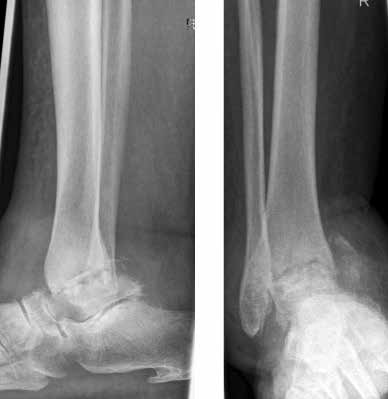

Arthrose stellt weltweit die häufigste Gelenkerkrankung dar und hat damit einen wesentlichen sozioökomischen Einfluss 1. Während 15 % der weltweiten erwachsenen Bevölkerung von Arthrose betroffen sind 2, leiden lediglich 1 % der Bevölkerung 3 bzw. 4,4 % der Arthrosepatienten 4 an einer Arthrose des oberen Sprunggelenks (OSG). Circa 80 % der Arthrosen des OSG sind ursächlich als posttraumatisch einzustufen, nur 9 % gelten als primäre Arthrosen. Dies unterscheidet die Arthrose des OSG von Coxarthrose (58 % primär) und Gonarthrose (67 % primär). 13 % treten im Rahmen systemischer Erkrankungen wie rheumatoider Arthritis, Hämochromatose, Hämophilie oder Osteonekrose auf 5 6. Die posttraumatische Arthrose des OSG wird besonders nach in Achsabweichung verheilten Frakturen (Pilon-tibiale-Frakturen, Weber-A‑, ‑B- und ‑C-Frakturen; Abb. 1a), Bandinstabilitäten des lateralen und medialen Bandapparates des OSG (Lig. fibulotalare anterius, Lig. fibulocalcaneare, Lig. fibulotibiale posterius etc.), nach rezidivierenden ligamentären Verletzungen sowie nach Gelenkverletzungen mit Knorpelschaden, „flake fractures“ oder „bone bruise“ beobachtet 7. Daher ist bei den vergleichsweise häufigen Weber-B- und ‑C-Frakturen die osteosynthetische Versorgung mittels Drittelrohrplatte und Zugschraube (Abb. 1b) sowie ggf. Syndesmosennaht mit Implantation einer Stellschraube mit millimetergenauer Reposition essentiell, um langfristig die Funktionsfähigkeit des OSG aufrechtzuerhalten und eine frühzeitige posttraumatische Arthrose zu verhindern 8.

Das besondere Merkmal der Arthrose des OSG ist das relativ junge Alter der Patienten im Vergleich zur Arthrose anderer Gelenke der unteren Extremität, da die meistens zugrunde liegenden Traumata Sportunfälle sind. Zusätzlich werden ein schnellerer Funktionsverlust des Gelenks und eine beschleunigte Progression der Erkrankung bis zum Erreichen des Endstadiums (innerhalb von 10 bis 20 Jahren) beobachtet 9 (Abb. 2a). Negativ beeinflussende Faktoren für die Entwicklung einer Arthrose des OSG sind: Achsfehlstellungen oder angeborene Deformitäten der unteren Extremität, Muskeldysbalance 10, angeborene oder erworbene ligamentäre Fehlentwicklungen, Alter, Geschlecht und genetische Prädisposition 11.